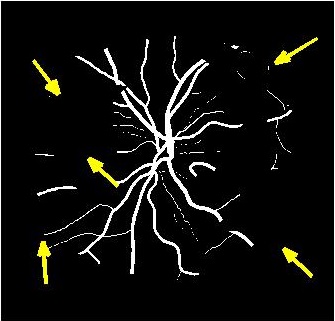

Results of fold cross validation for are presented in Table 1. Due to space constraints only SSIM values are shown for . For , performance difference of all methods is small but becomes more pronounced for higher . gives the best results for all , and the improvement over competing methods is significant as is evident from the values of Wilcoxon signed-rank tests. Figure 3 shows results of the top methods (due to space constraints) for . shows the best performance as is evident from the SR image in Fig. 3 (b) where one of the minor retinal branches (indicated by yellow arrow) is clearly visible. On the other hand the SR image by (Fig. 3 (c)) is blurry and does not clearly show this retinal branch. Other methods perform much worse, with significant blur visible for the main branches as well. Clearly, gives the closest reconstruction to the HR image of Fig. 3 (a).

4.2 Retinal Blood Vessel Segmentation Results

We present retinal vessel segmentation results on the DRIVE [16], STARE [6] and CHASEDB1 [5] datasets with , and images respectively. Original images and manual annotations () are downsampled by to get and sets of from methods trained on [2]. and the sets of were used to train different state-of-the art U-Nets for vasculature segmentation [1]. The average accuracy () and sensitivity () for is summarized in Table 2. Better ISR methods should give higher vessel segmentation accuracy and performance of gives a lower bound on the segmentation error. ’s performance is closest to , and establishes its superiority over all competing methods. Figures 4 (a)-(h) show results of vessel segmentation on an example image. ’s performance is most similar to as is evident from the areas of inaccurate segmentation highlighted by yellow arrows. Most of the methods do not segment the finer vasculature structures, while SSR and SR-RF are unable to segment some of the major arteries.